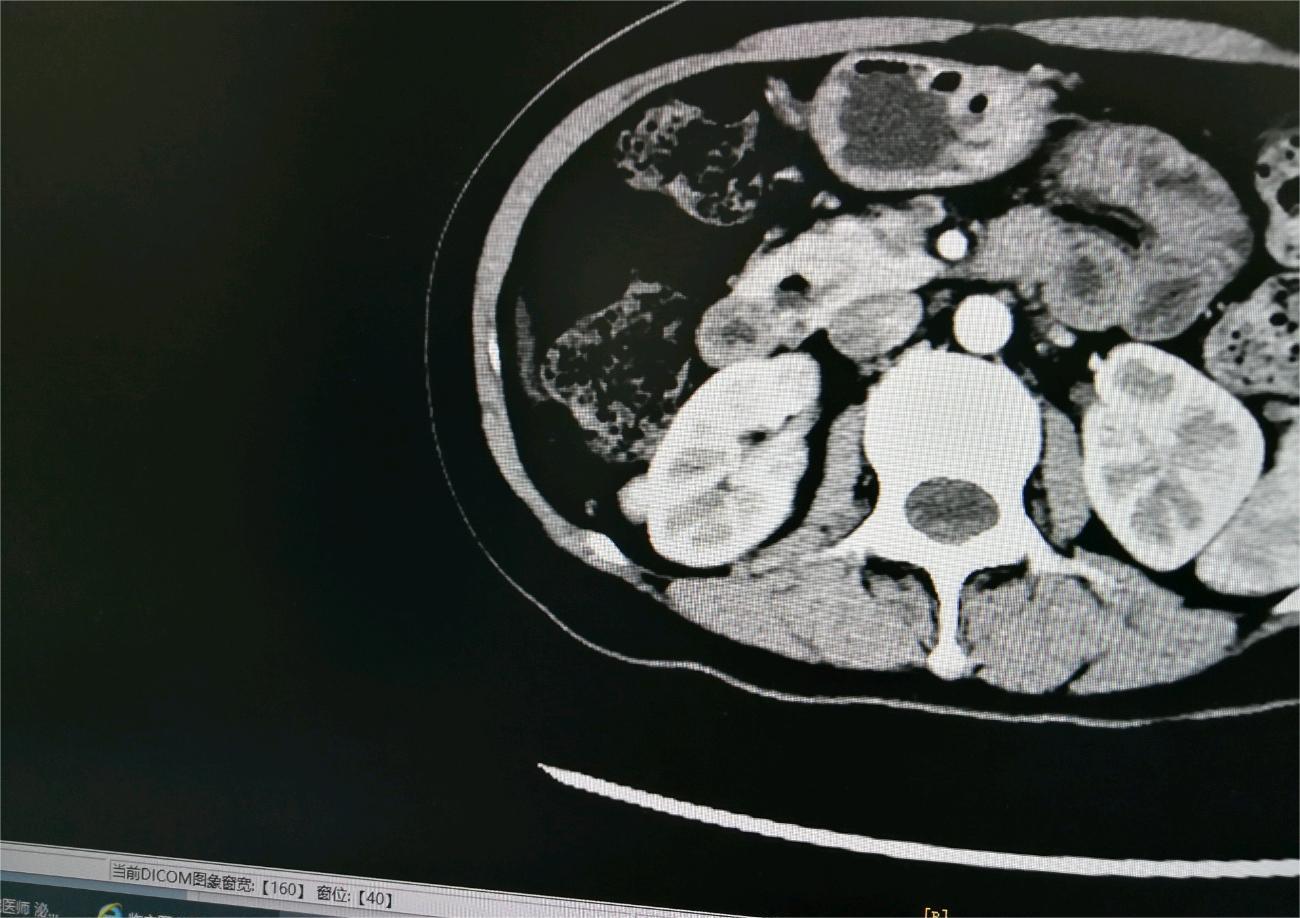

雪落下的季节 02025-02-11 患者家属爸1月份突然出现腰疼不能走路的情况,到医院做检查后发现右肾有个4厘米的肿瘤,怀疑是转移到腰椎!做加强ct后发现腰椎确...